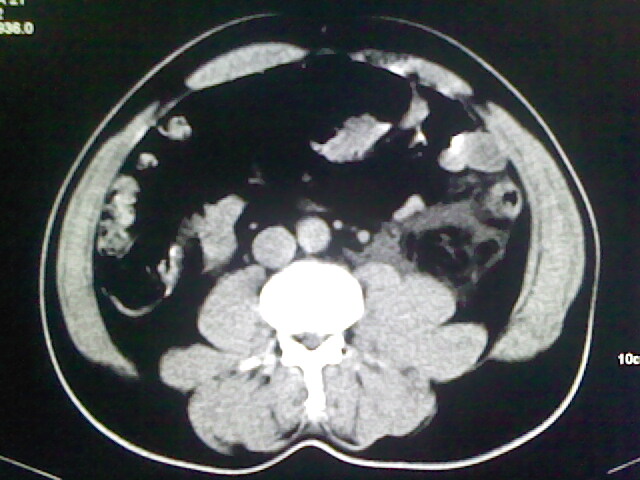

以下是引用zsl6918在2009-2-7 7:29:00的发言:[br]请提供介入的方式方法,肾及输尿管改变考虑与介入损伤有关,漏了,尿液外渗。

以下是引用余辉在2009-2-7 8:27:00的发言:[br]可能是硬化剂烧穿囊壁进入肾盂输尿管了,尿漏。不除外介入或碎石术后合并感染[br]患者术后怀疑结石,接着就碎石了?就怀疑没有确诊吗?碎石用的什么方法?气压弹道还是体外超声?如果这样的话责任人都难找

以下是引用随光逐影在2009-2-7 8:46:00的发言:[br]支持3楼意见。[br]另:不排除左肾及肾周感染可能。